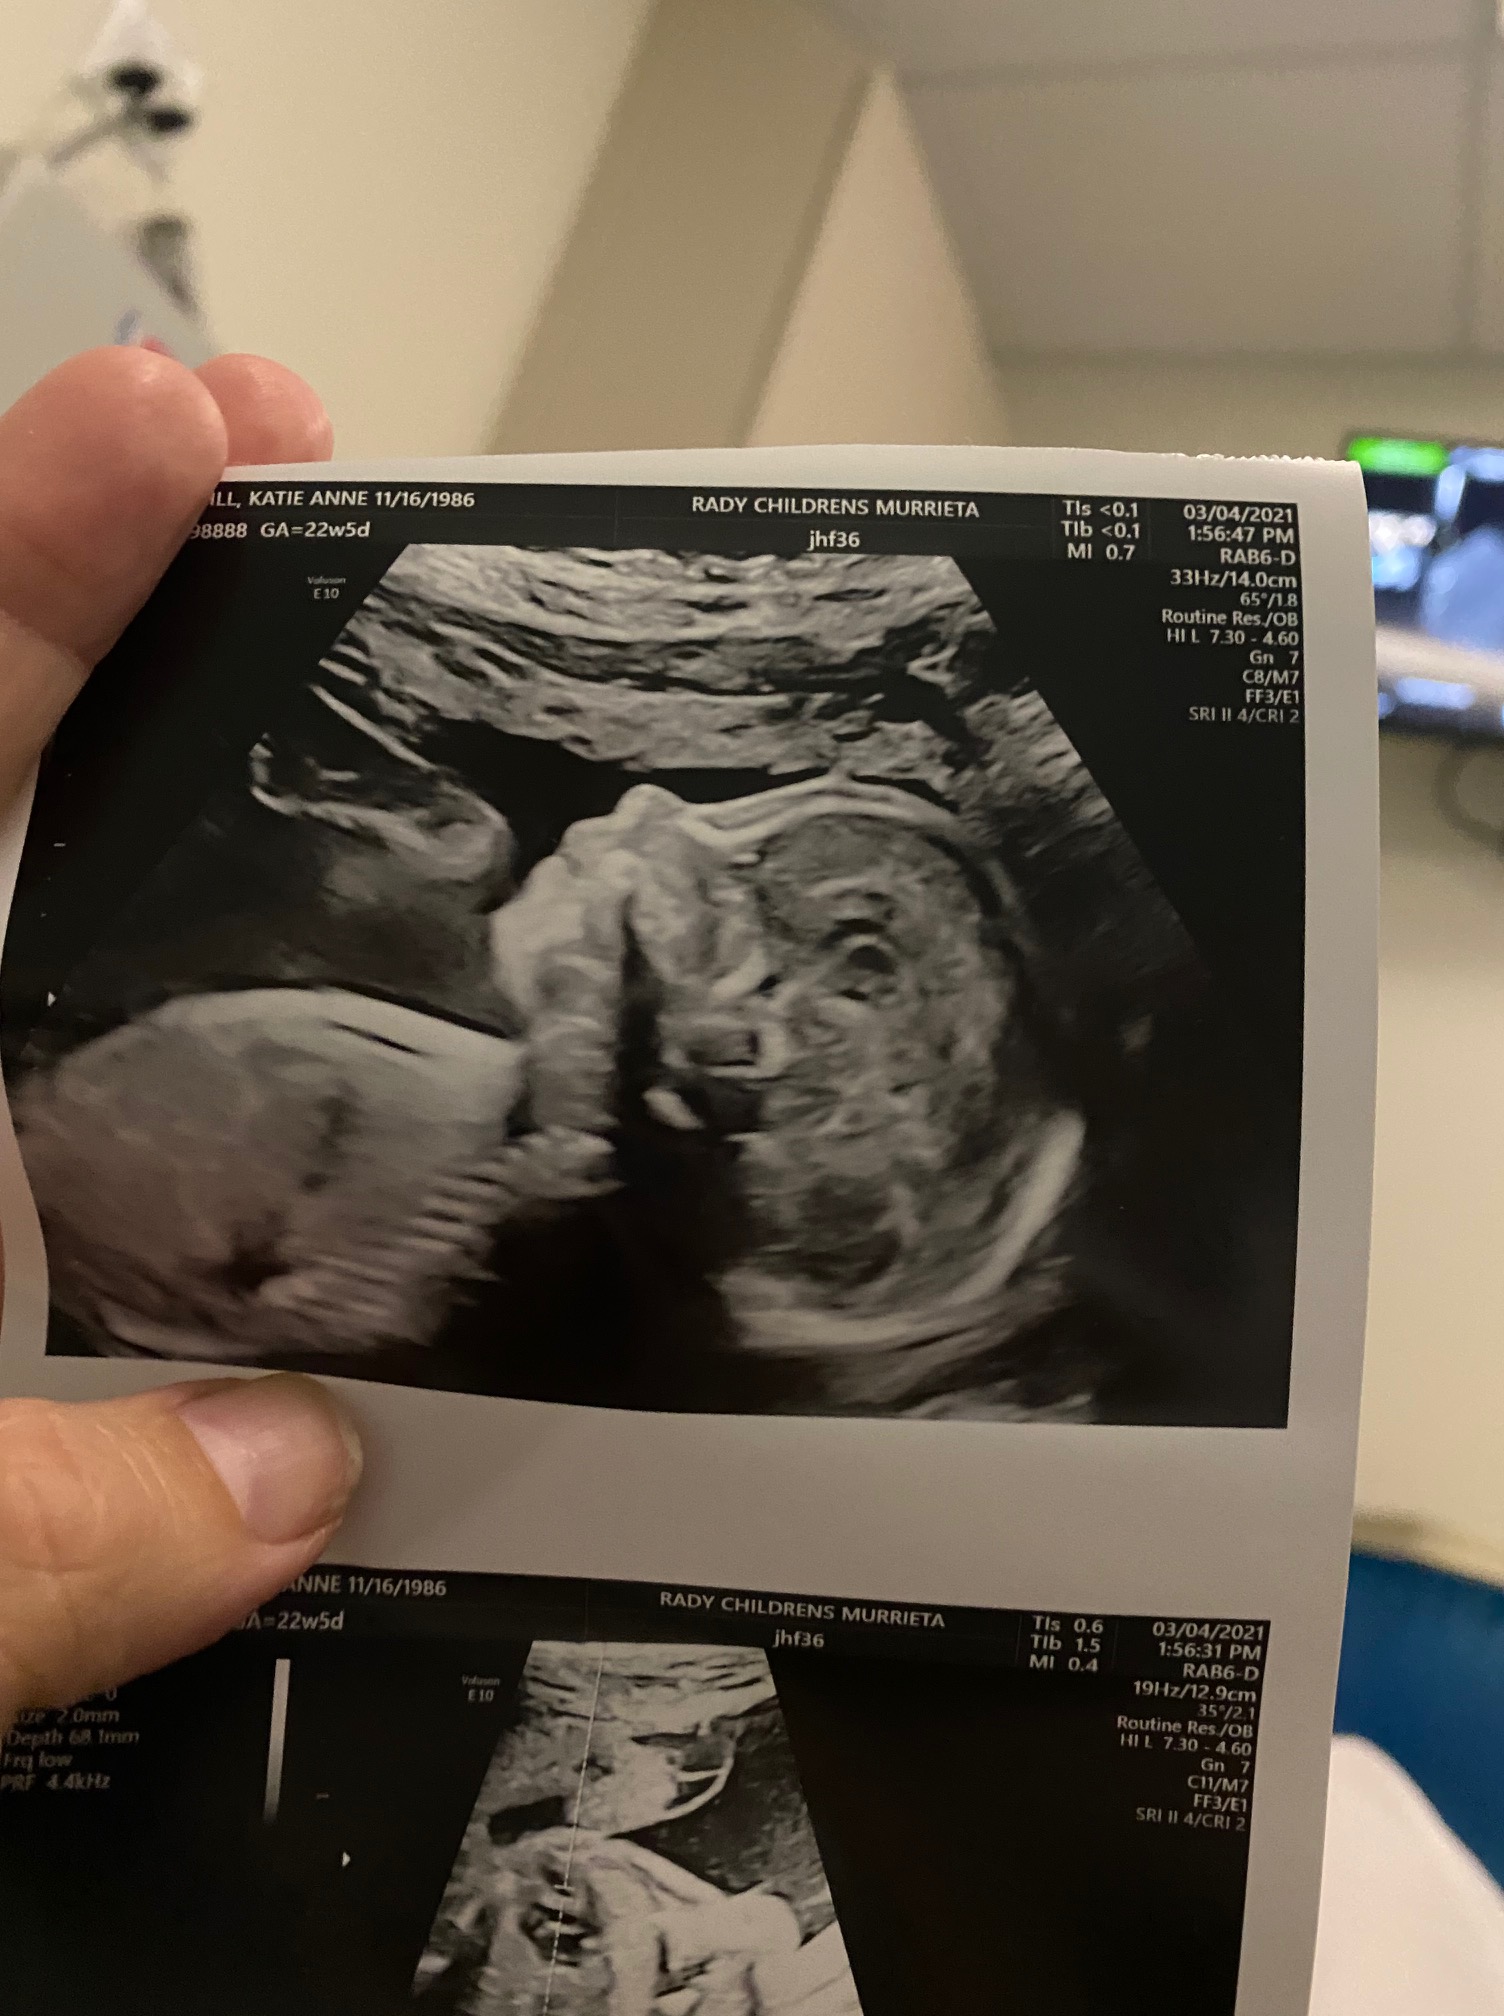

you have also known that, if we were to pursue parenthood, our pathway would be…clinical. and turns out, it would also end up involving a whole other family and a whole other womb. our surrogate katie is amazing, as one might guess in this instance. a NICU nurse and mom of 3, she fell into surrogacy (in as much as that can happen) and perhaps we were meant to find each other, matching only 4 days into what’s typically at least a 6-month process. and, in appreciation of science, technology and freezers with back-up generators, our embryos that we created in 2012 were still viable. out of 3 that grew out and made it through testing, 2 were boys and 1 was a girl. we asked them to implant the best one, the one that would have the highest chance of success, because we were only going to do this once. we would just plan be surprised later. it turns out the girl embryo was the best.

i imagine i’ll keep my permanent blog up when i can, as my creative space to process what is happening in the world around me and inside my own life experience. in the meantime, i’m sharing a piece i contributed to a magazine, Wildfire, about becoming a parent and moving towards closure with choosing the pathway of surrogacy. it follows one of our recent sonogram pictures.